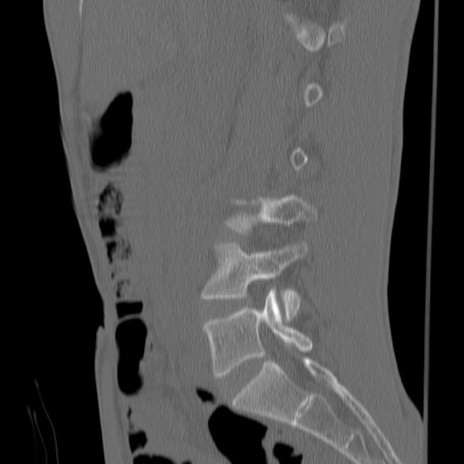

症例3 腰椎CT(矢状断像)

【症例】30歳代男性

【主訴】腰痛

【現病歴】本日旅行先で観光中に、友人と衝突し転倒し受傷。

【身体所見】麻痺なし、右下腿内側前面外側、左下腿内側に知覚鈍麻・しびれ

異常所見と診断は?

腰椎CT